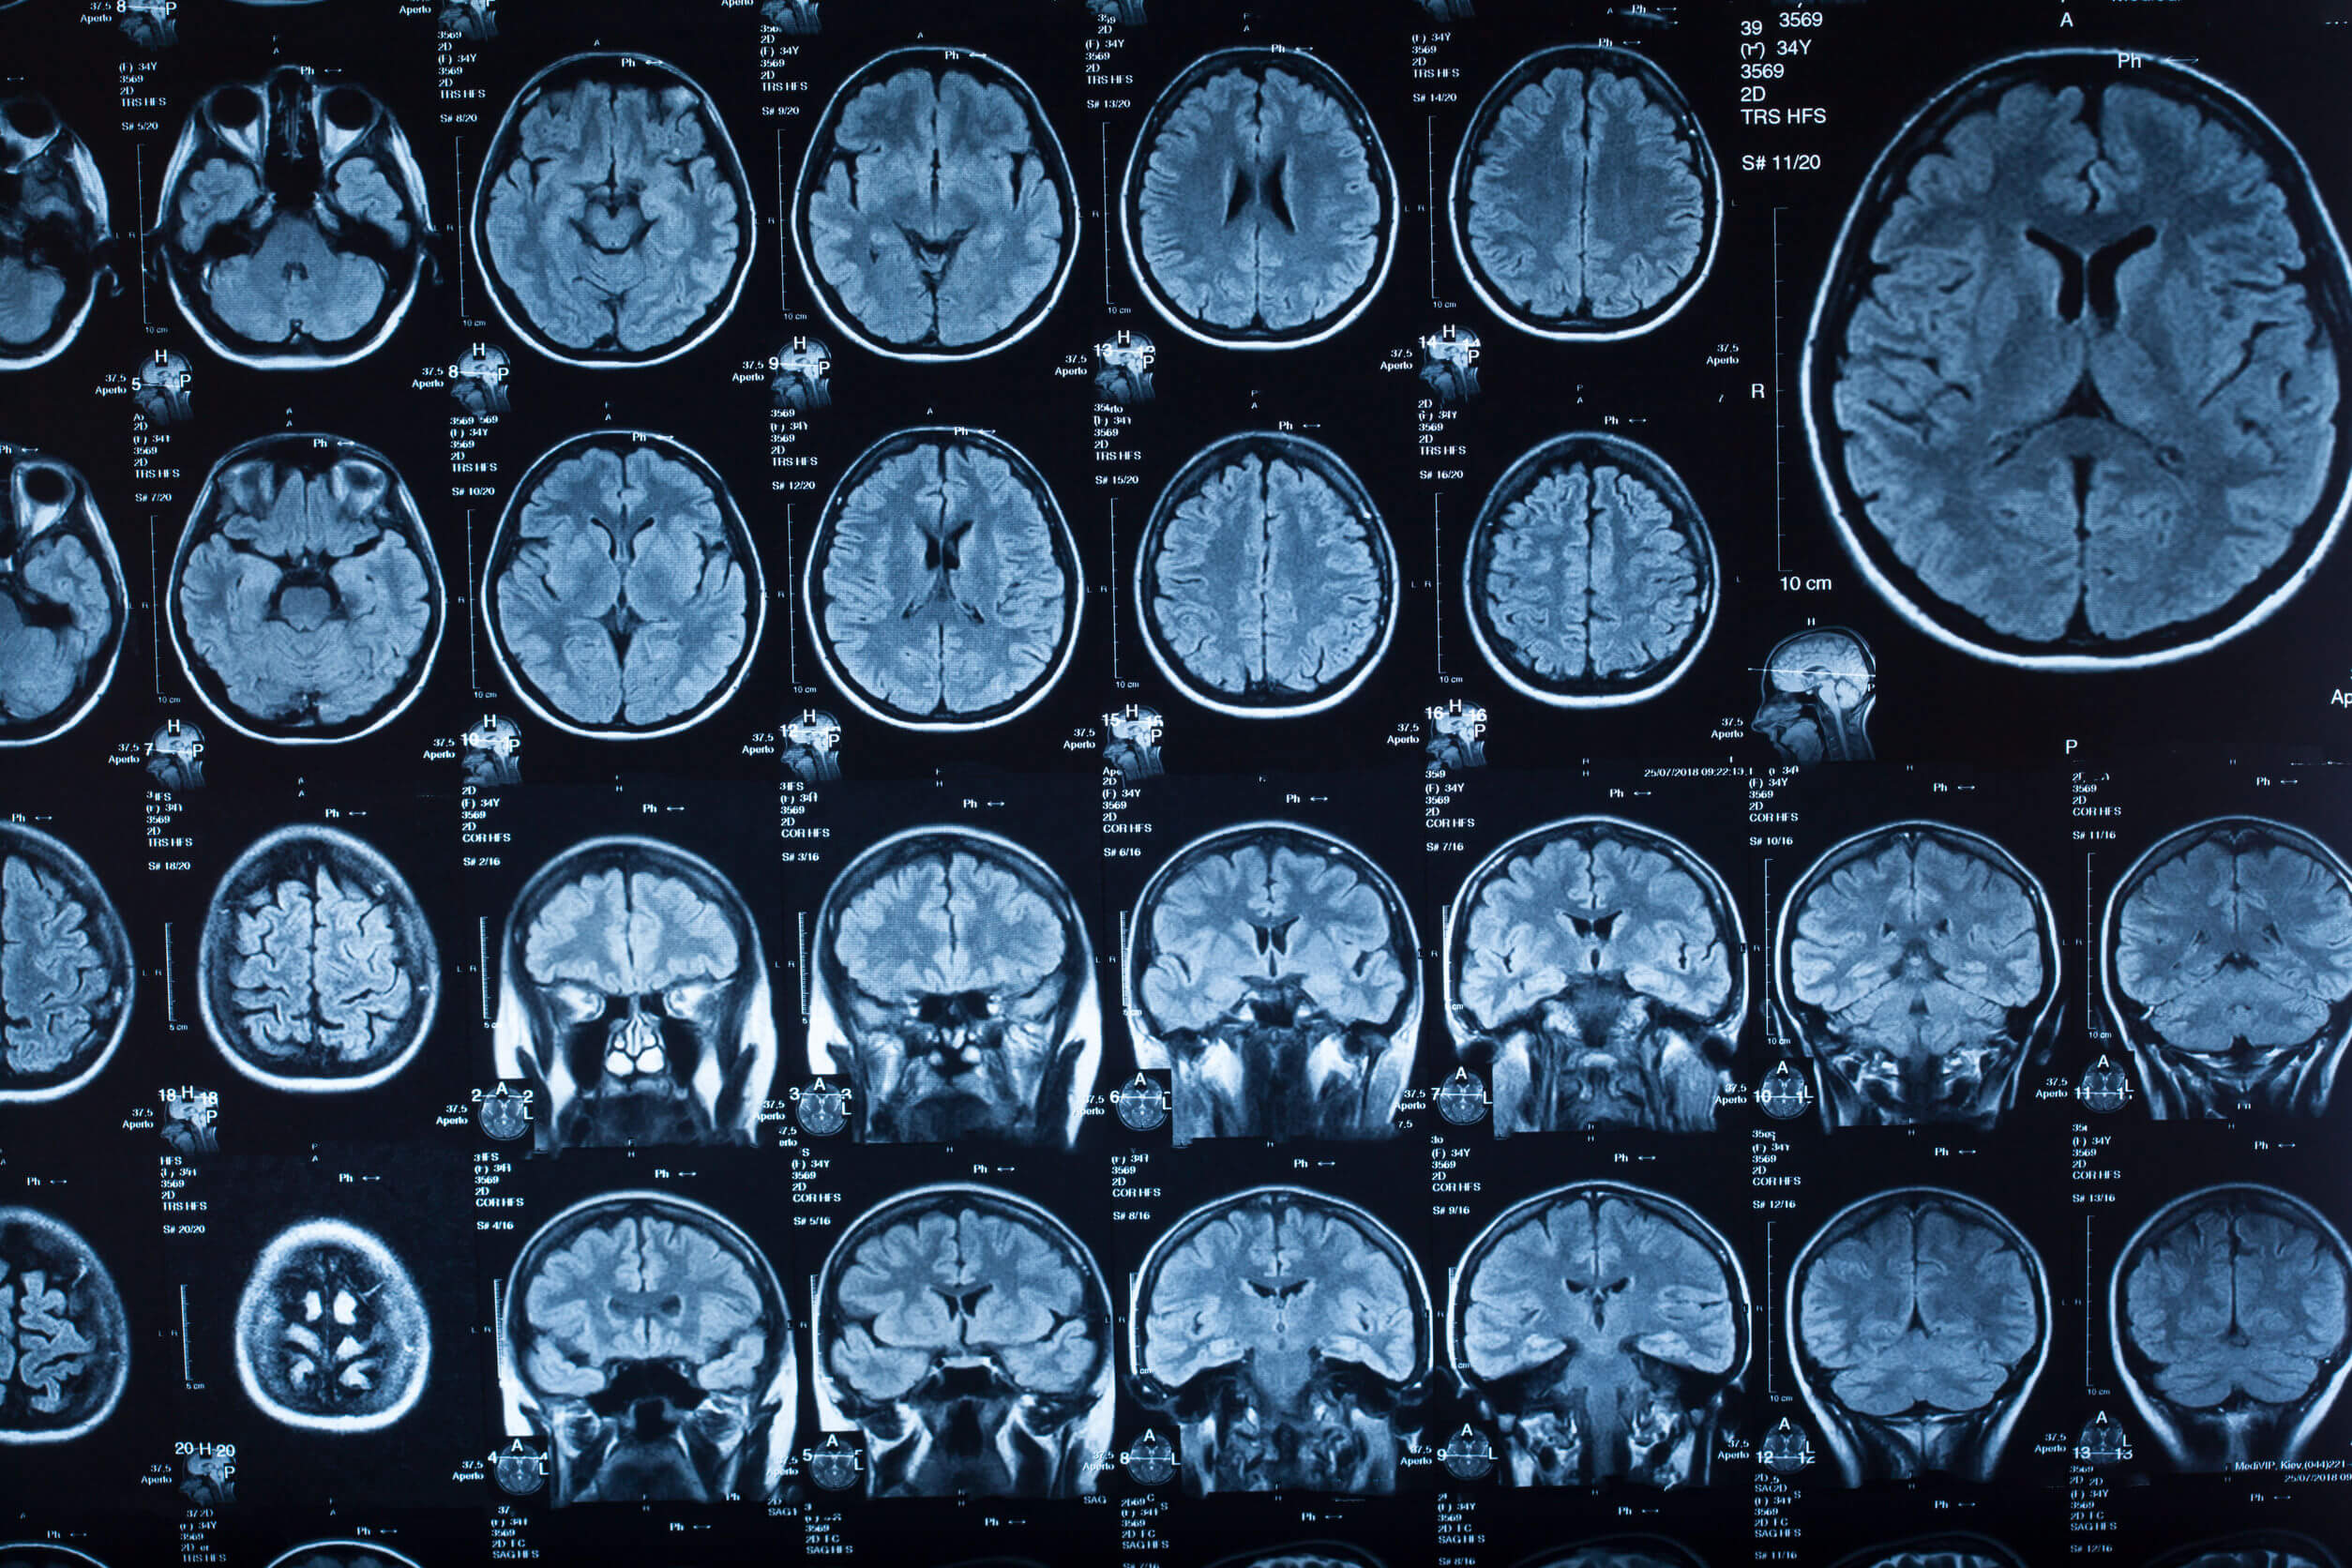

- Resonancia magnética: también se usa para descartar otras complicaciones subyacentes, aunque enfocada en el área de la columna vertebral puede arrojar pistas sobre la inflamación de las meninges.